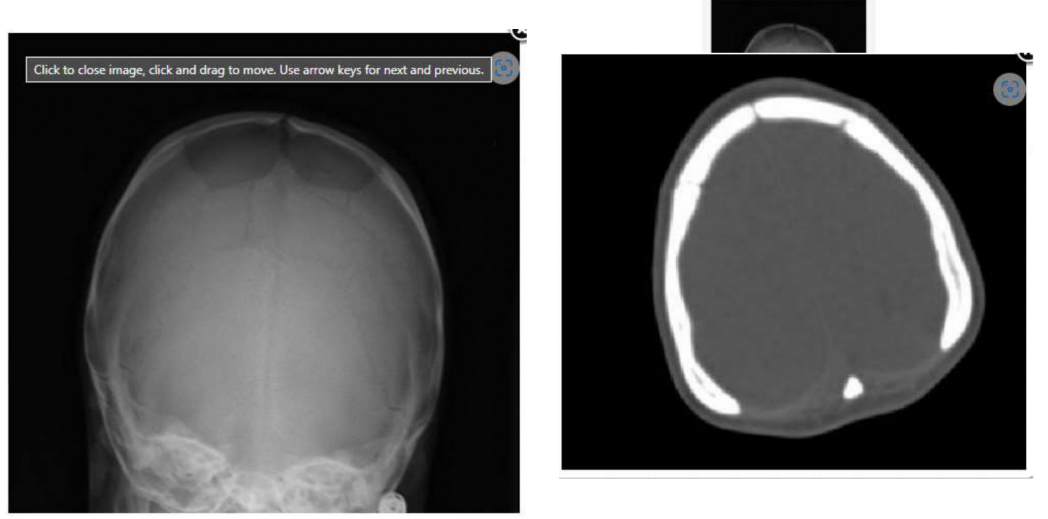

A 6-year-old with Down syndrome has a skull defect that has been present since birth (Figures 1 & 2). What is the correct diagnosis?

a. Aplasia cutis congenita

b. Acute skull fracture

c. Dermoid cyst

d. Healed skull fracture

e. Bilateral parietal foramina

A

Bilateral parietal foramina